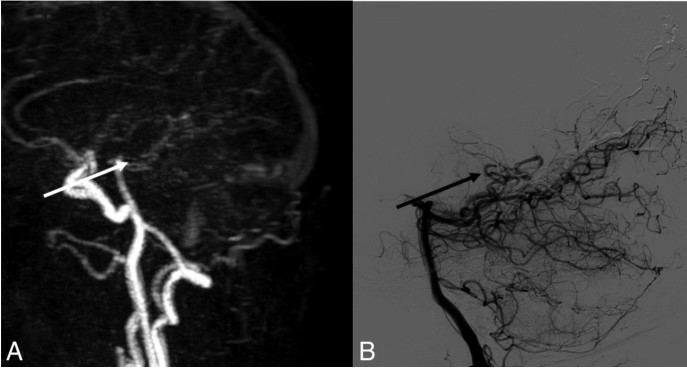

图2. A.动脉期4D-MRA矢状位。B.经左侧椎动脉行脑血管造影矢状面。A中的白色箭头和B中的黑色箭头显示早期静脉显影,出现在上矢状窦显影前,应为动静脉分流。